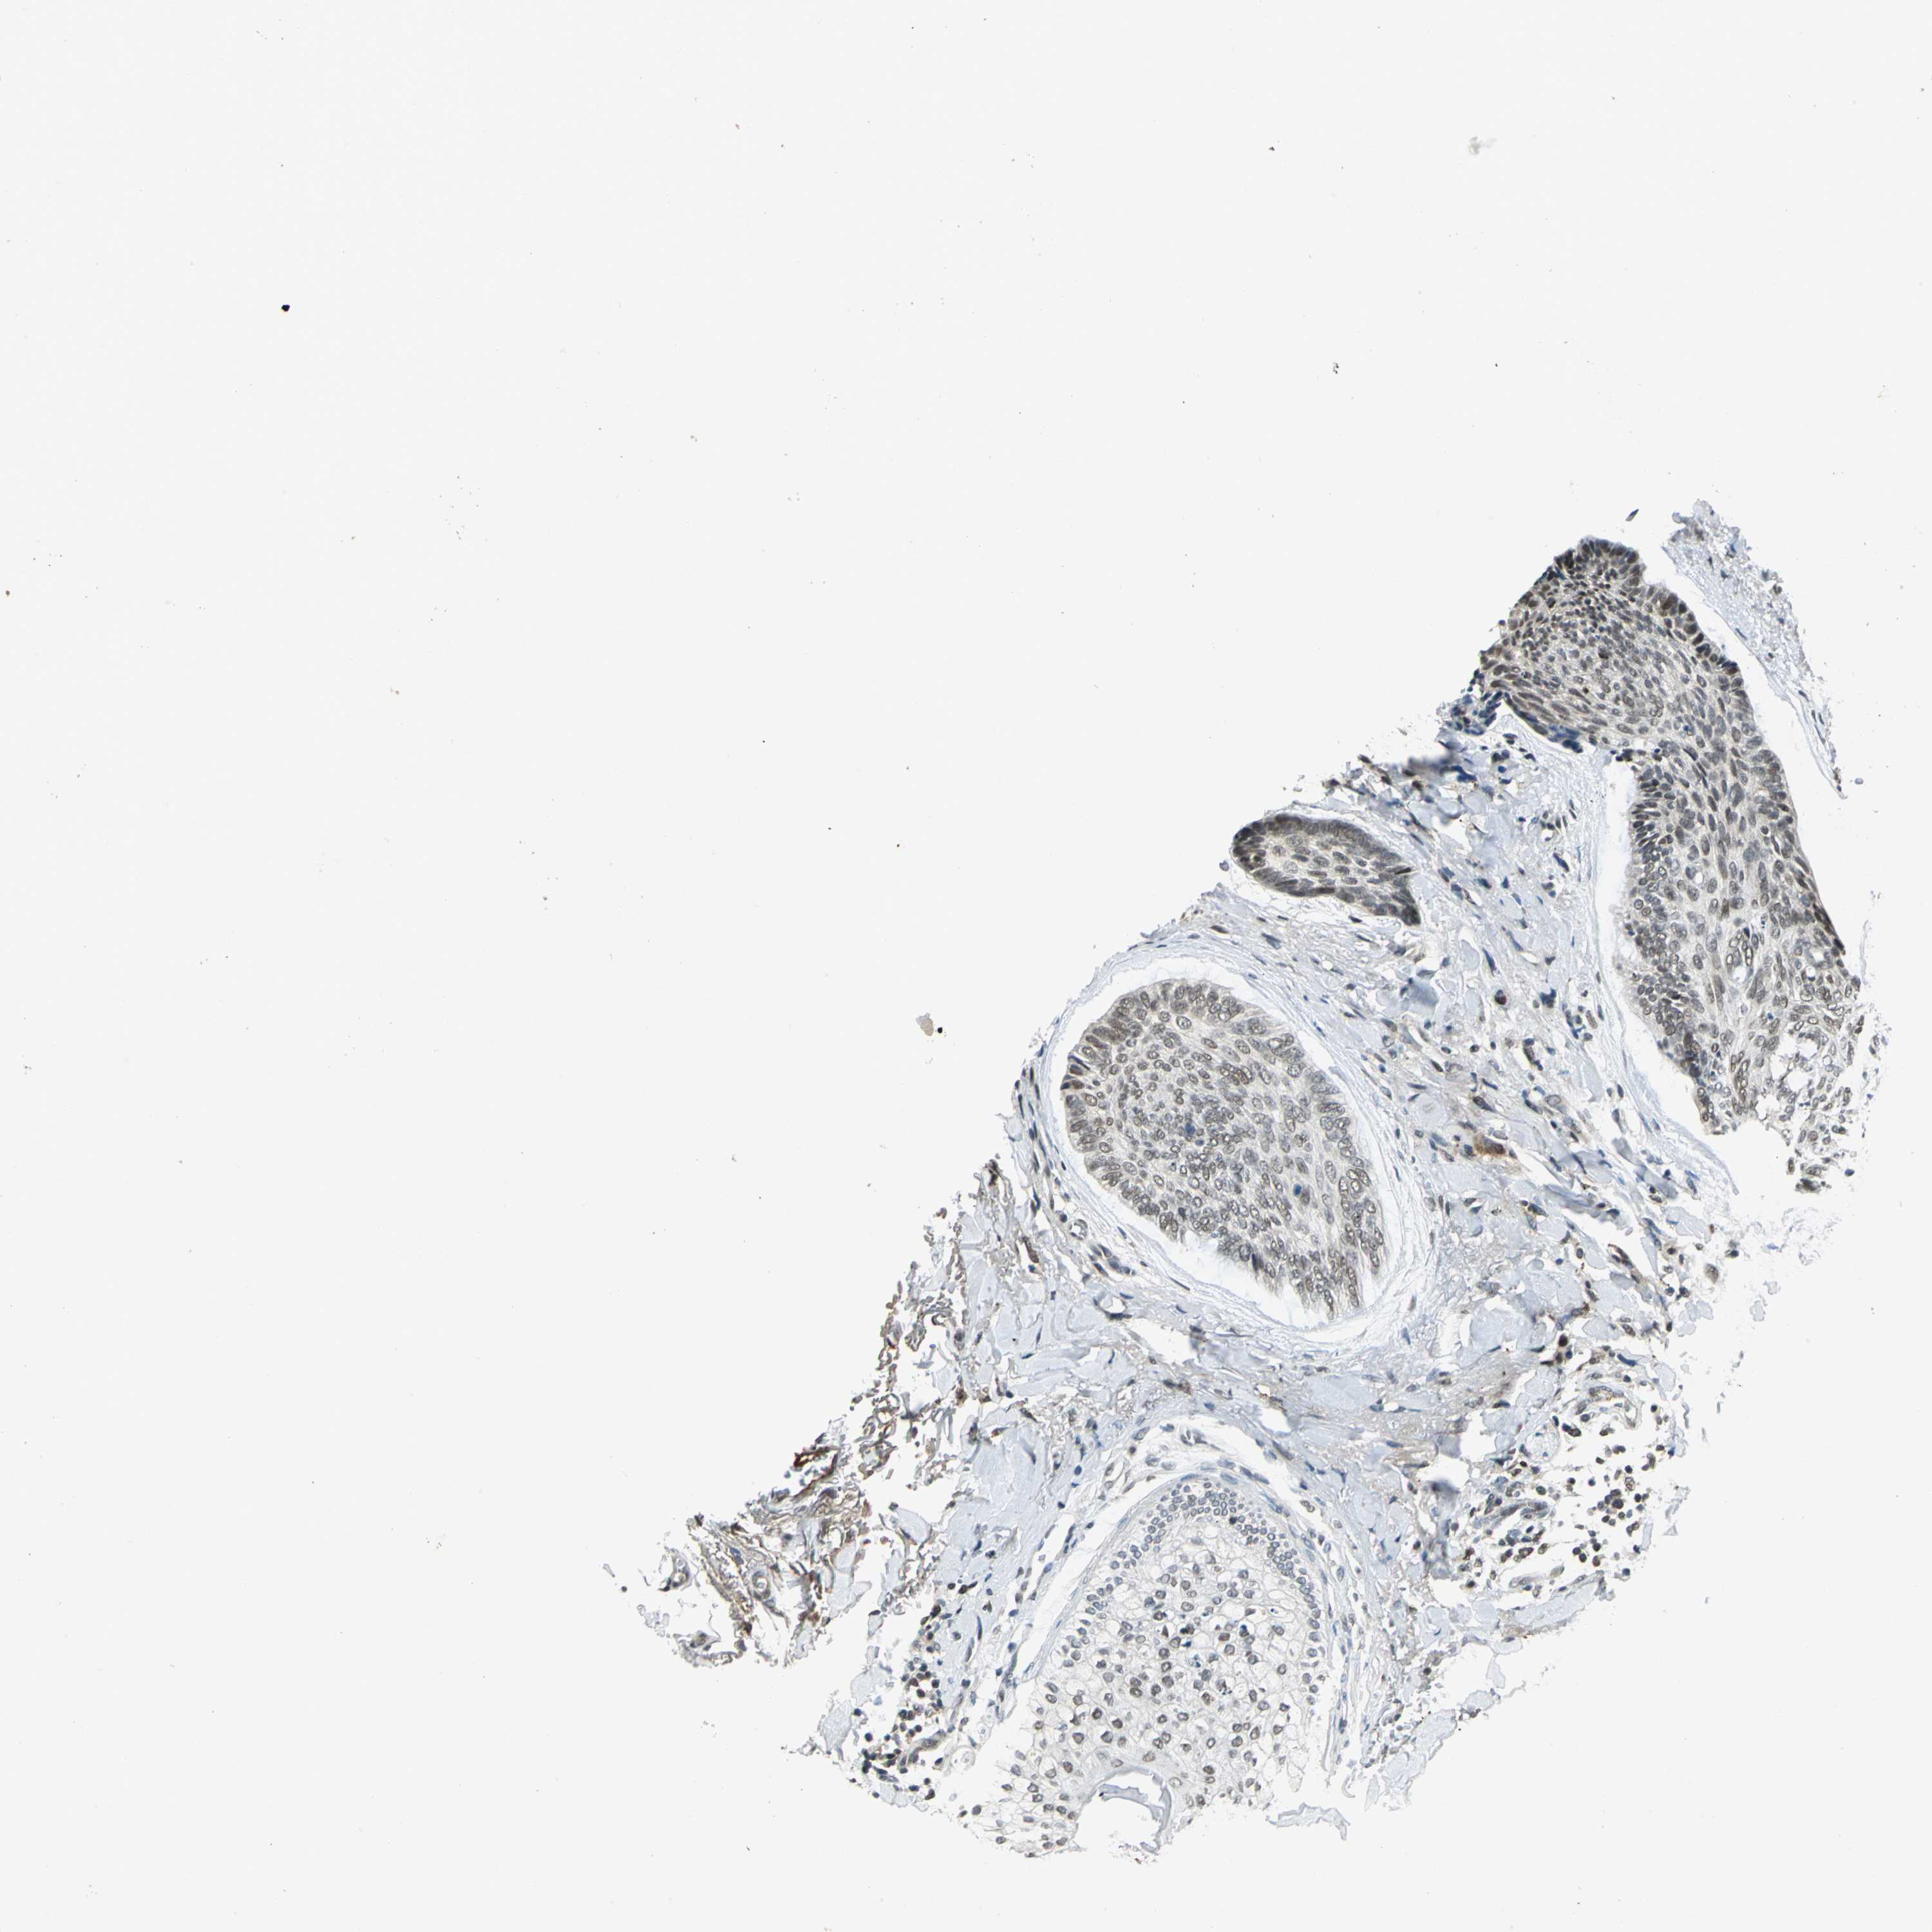

CANCER SKIN CANCER Show tissue menu

Basal cell and squamous cell cancer

SKIN CANCER - Protein expressioni

A mouse-over function shows sample information and annotation data. Click on an image to view it in a full screen mode. Samples can be filtered based on level of antibody staining by selecting one or several of the following categories: high, medium, low and not detected. The assay and annotation is described here.

Antibody stainingi

Antibody staining in the annotated cell types in the current human tissue is reported as not detected, low, medium, or high, based on conventional immunohistochemistry profiling in selected tissues. This score is based on the combination of the staining intensity and fraction of stained cells.

Each image is clickable and will lead to virtual microscopy that enables deeper exploration of all samples and also displays staining intensity scores, fraction scores and subcellular localization as well as patient and tissue information for each sample.

Antibody HPA005448

Antibody CAB004551

Staining

High

Medium

Low

Not detected

Intensity

Strong

Moderate

Weak

Negative

Quantity

>75%

75%-25%

<25%

None

Location

Nuclear

Cytoplasmic/membranous

Cytoplasmic/membranous,nuclear

Squamous cell carcinoma, NOS

Basal cell carcinoma